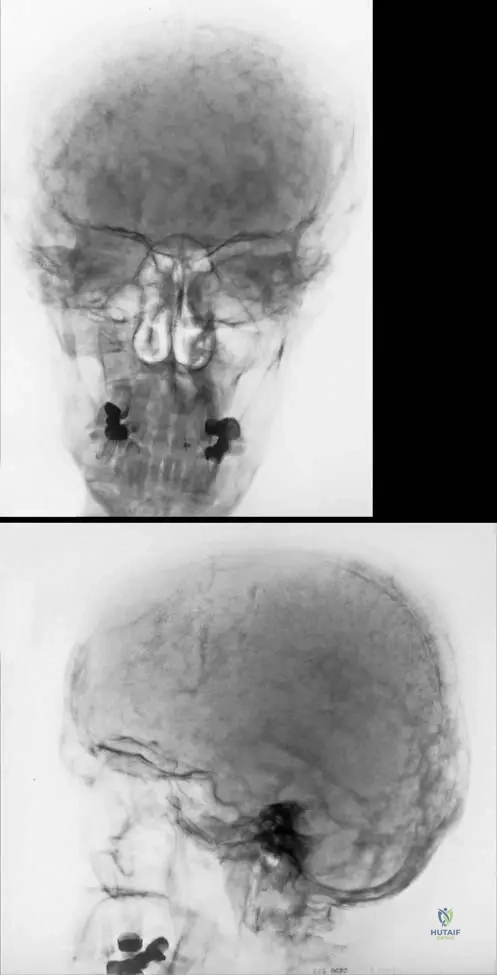

A 70-year-old male presents with a history of progressive hearing loss and increasing hat size. A skull radiograph is performed. Which of the following radiographic findings would be most characteristic of the acute phase of Paget's disease in the skull?

Correct Answer: C

Rationale: The image caption (Fig. 7.54 a, b) explicitly states, "The skull shows typical changes in the acute phase known as osteoporosis circumscripta." This refers to well-demarcated lytic lesions in the skull. While "cotton wool appearance" (A) and sclerotic patches (D) are also seen in Paget's, they are typically associated with later, mixed, or sclerotic phases. Punched-out lytic lesions (B) are more characteristic of multiple myeloma. Hair-on-end appearance (E) is seen in conditions like thalassemia.